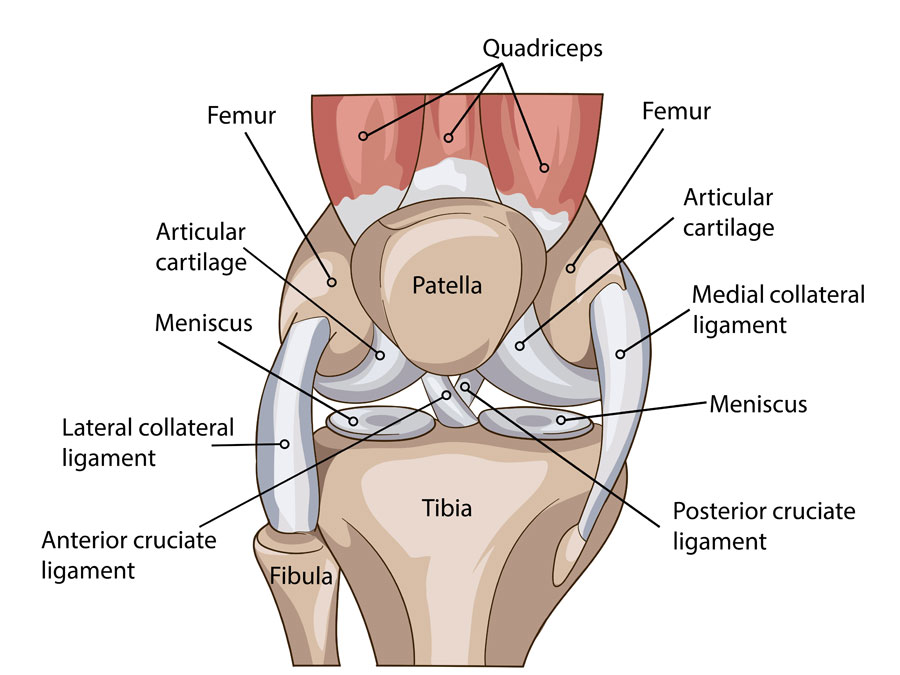

Your Meniscus is: Made of two wedge-shaped pieces of tough and rubbery cartilage that act as “shock absorbers” between your thighbone (femur) and shinbone (tibia).

- Bucket handle tear: A complete tear of the meniscus’ inner rim that moves into the center of the knee from the periphery.

- Flap or “Parrot beak” tear : A flap or “parrot beak” meniscal tear is when the tendon remains connected in one plane, and displaced in the other. On scan images this type of tear is curved like a crescent, hence the name “parrot’s beak” tear.

- Radial tear: A tear across the meniscal circumference.

The outside third of the meniscus has a rich blood supply, meaning a small tear in this “red” zone may heal on its own, or can often be successfully repaired with surgery.

The inner two-thirds of the meniscus lack this beneficial blood supply and without the necessary nutrients, tears in this “white” zone cannot heal. Because the pieces cannot grow back together, tears in this zone are usually surgically trimmed away.